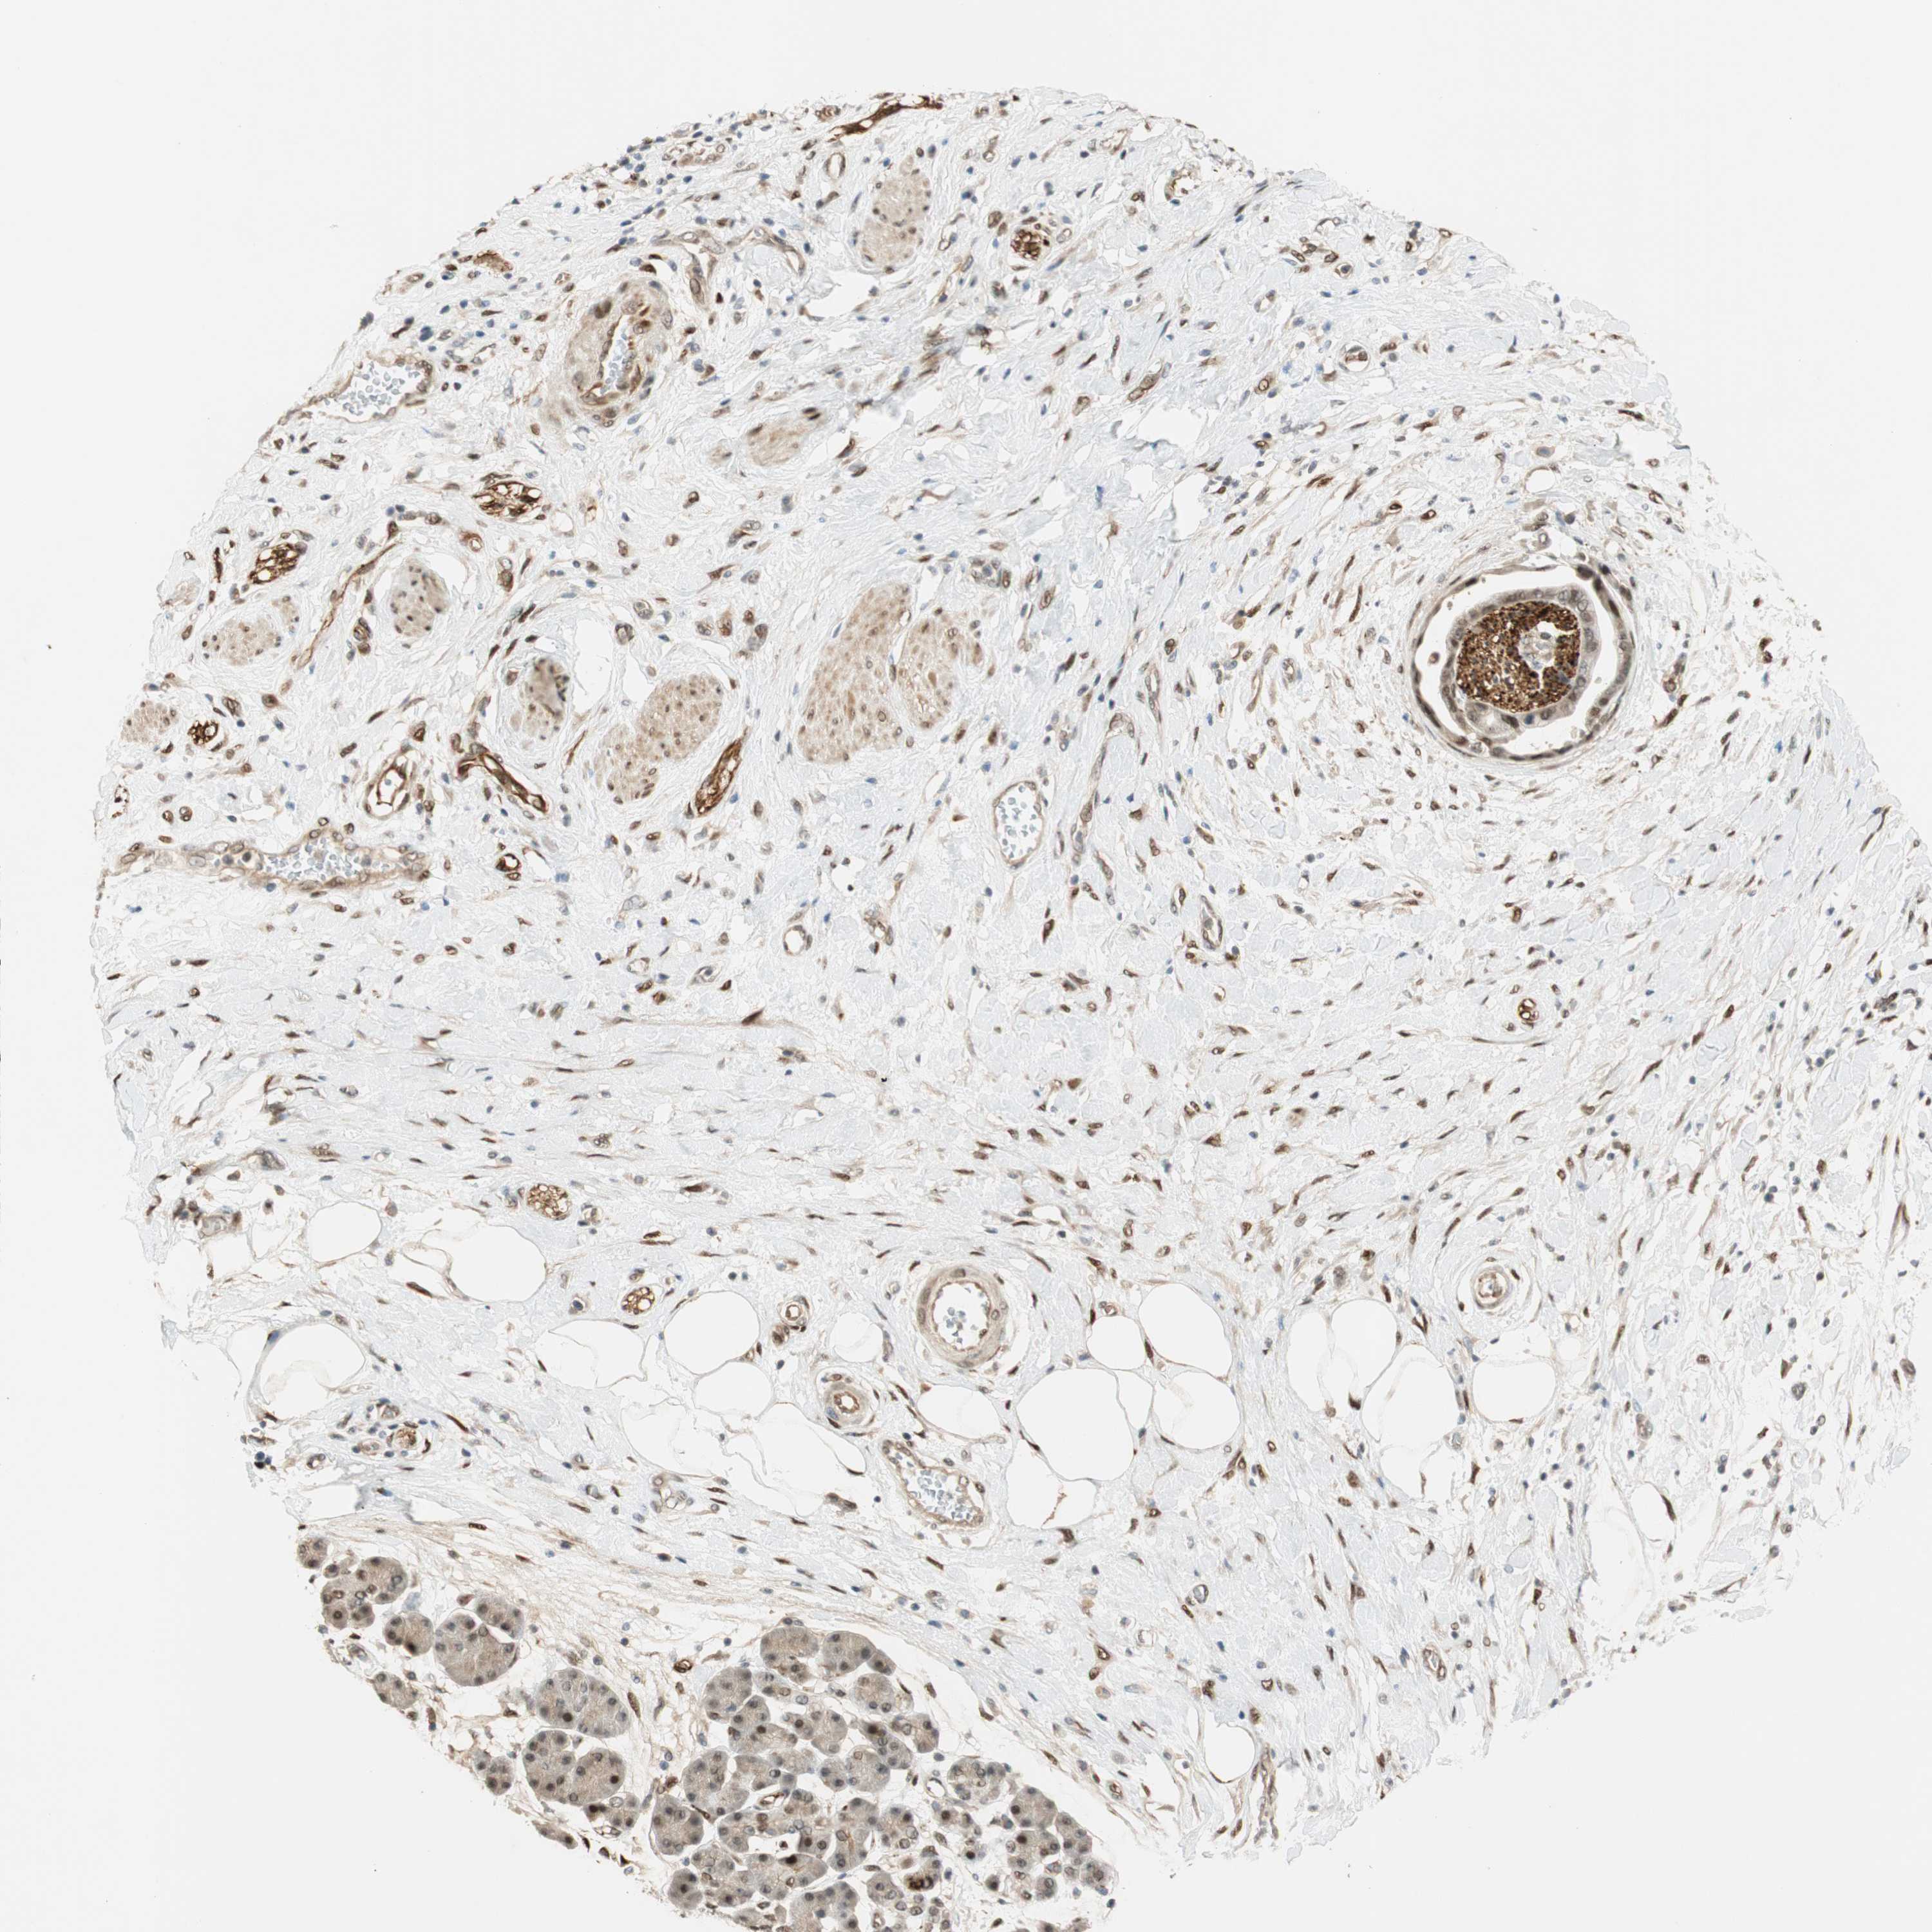

PANCREATIC CANCER - Protein expressioni

A mouse-over function shows sample information and annotation data. Click on an image to view it in a full screen mode. Samples can be filtered based on level of antibody staining by selecting one or several of the following categories: high, medium, low and not detected. The assay and annotation is described here.

Note that samples used for immunohistochemistry by the Human Protein Atlas do not correspond to samples in the TCGA dataset.

Antibody stainingi

Antibody staining in the annotated cell types in the current human tissue is reported as not detected, low, medium, or high, based on conventional immunohistochemistry profiling in selected tissues. This score is based on the combination of the staining intensity and fraction of stained cells.

Each image is clickable and will lead to virtual microscopy that enables deeper exploration of all samples and also displays staining intensity scores, fraction scores and subcellular localization as well as patient and tissue information for each sample.

Antibody HPA007007

Antibody HPA026111

Antibody CAB005889

Antibody CAB058692

Staining

High

Medium

Low

Not detected

Intensity

Strong

Moderate

Weak

Negative

Quantity

>75%

75%-25%

<25%

None

Location

Nuclear

Cytoplasmic/membranous

Cytoplasmic/membranous,nuclear

Adenocarcinoma, NOS

Adenocarcinoma, metastatic, NOS